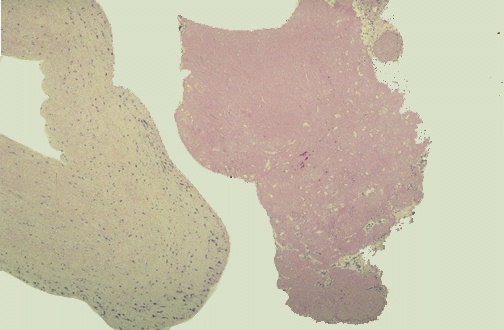

| The cardiac valve is seen on the left, and a bland vegetation is seen on the right. It appears pink because it is composed of fibrin and platelets. It displays about as much morphologic variation as a brown paper bag. Such bland vegetations are typical of the non-infective forms of endocarditis. |